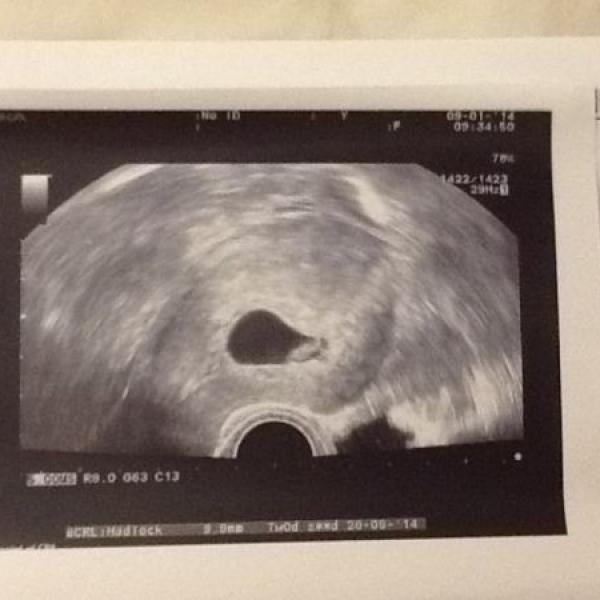

Ahoj holky ze srpňátek i vśechny ostatní,které to zajímá :a: všechny zdravím a přikládám fotečky našeho prcka. Bylo moc prima ho vidět,máme i 20 min dvd. :dance: kdo váhá doporučuju jako pěknou památku. Když jsem s malou byla později (26tt) tak byl vidět sice plnější obličejík,ale jinak záznam stál za prd.

:dance: tak to máme taky konečně za sebou :€s€: všechno vypadá dobře ,i když to bylo docela zdlouhavé. Prcek nechtěl moc spolupracovat,pak škytal tak nešel poměřit. Jen nebyly vidět prstíčky na rukou-nejspíš měl zavřené pěstičky :?

Taky říkala že v pupečníku jsou dvě cévy místo tří,tak se bude častěji kontrolovat jak roste. Prý je to docela časté. Další utz a kontrola v 16tt.